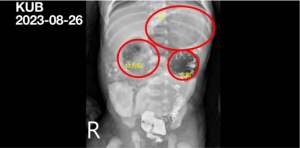

「腸道閉鎖」新生兒驚吐綠膽汁 花蓮慈院小兒科、小兒外科攜手解鎖

2023年8月出生的小寶(化名)還在媽媽肚子裡的時候,就經由產前檢查發現腹部腸道腫脹的問題,當時的婦產科團隊就建議要密切注意後續的發展,結果出生後小寶喝一口奶吐一口,除了完全無法進食之外,還嘔吐出綠色的膽汁,醫師診斷為新生兒腸道閉鎖,經由轉院來到花東地區唯一擁有小兒外科的花蓮慈濟醫院,由小兒部蕭宇超醫師、小兒外科楊筱惠醫師帶領團隊接手治療,術後十二天就康復出院。